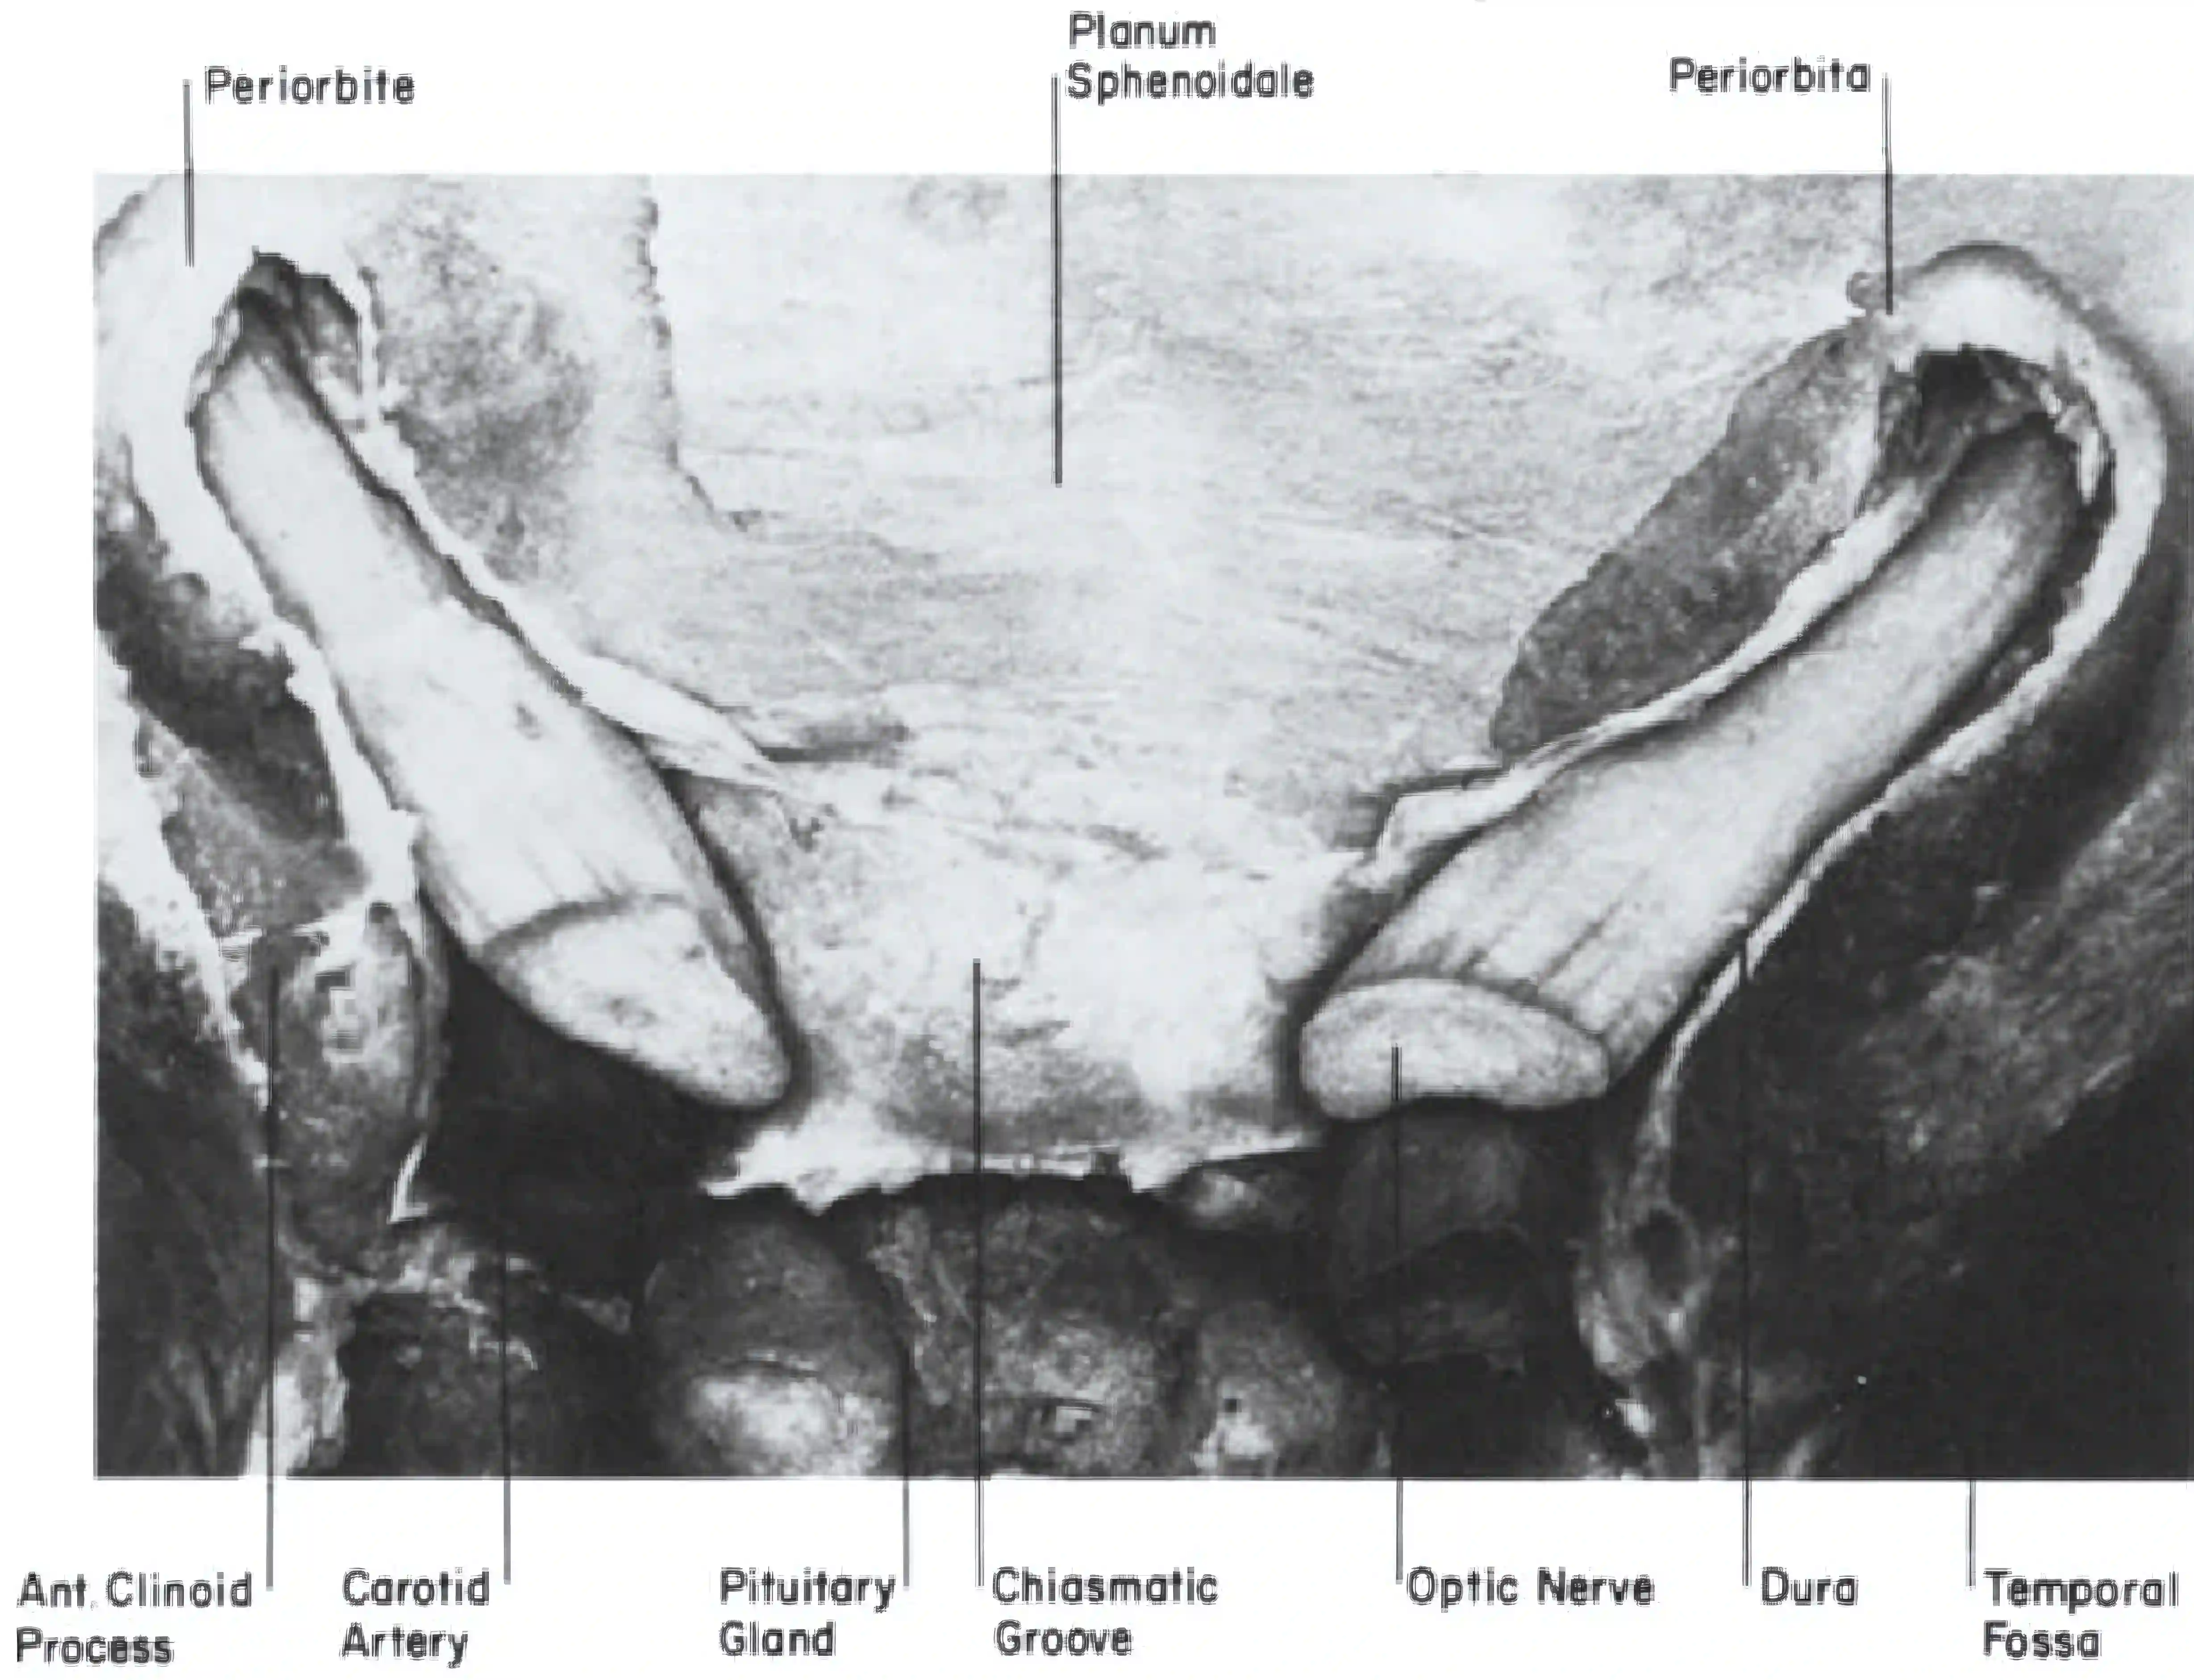

Intraoperativ

Intraoperativ dient der Nervus opticus als wichtige anatomische Orientierung bei neurochirurgischen Eingriffen.

Nervus opticus intraoperativ

Darstellung des linken Nervus opticus über einen modifizierten linksseitig lateralen supraorbitalen Zugang (modifizierter LSO).